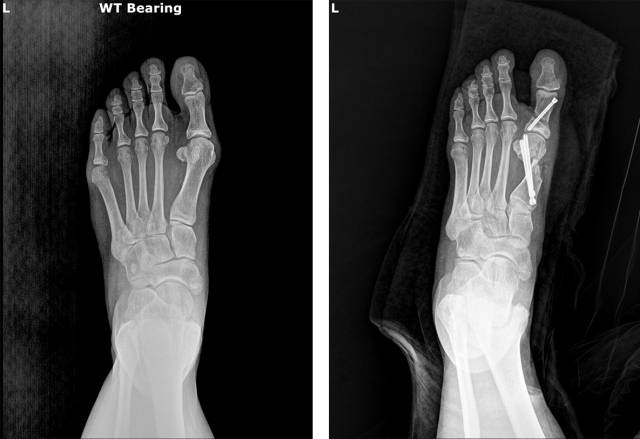

특히 변형이 심해진 상태에서는 뼈의 위치와 각도를 교정해 주어야 하며, 이를 위해 결국에는 수술을 선택할 수밖에 없다는 게 전문의들의 의견이다.

무지외반증의 치료법은 지속적인 연구와 학술 활동을 통해 발전해 왔는데, 최근 무지외반증에 적용되는 수술 방법으로는 절개 범위를 줄이고 회복을 빠르게 하는 최소침습 수술(MICA: Minimally Invasive Chevron-Akin Osteotomy)이 점차 널리 시행되고 있다.

약 1㎝ 미만의 작은 절개로 특수 기구를 넣어 뼈를 자르고 교정한 뒤, 실시간 투시 영상(C-arm)으로 교정 상태를 확인하며 나사로 고정한다. 보고된 장점으로는 출혈과 부종이 적고, 흉터가 거의 남지 않으며, 비교적 빠른 시기에 체중 부하와 일상생활 복귀가 가능하다는 점 등이다.